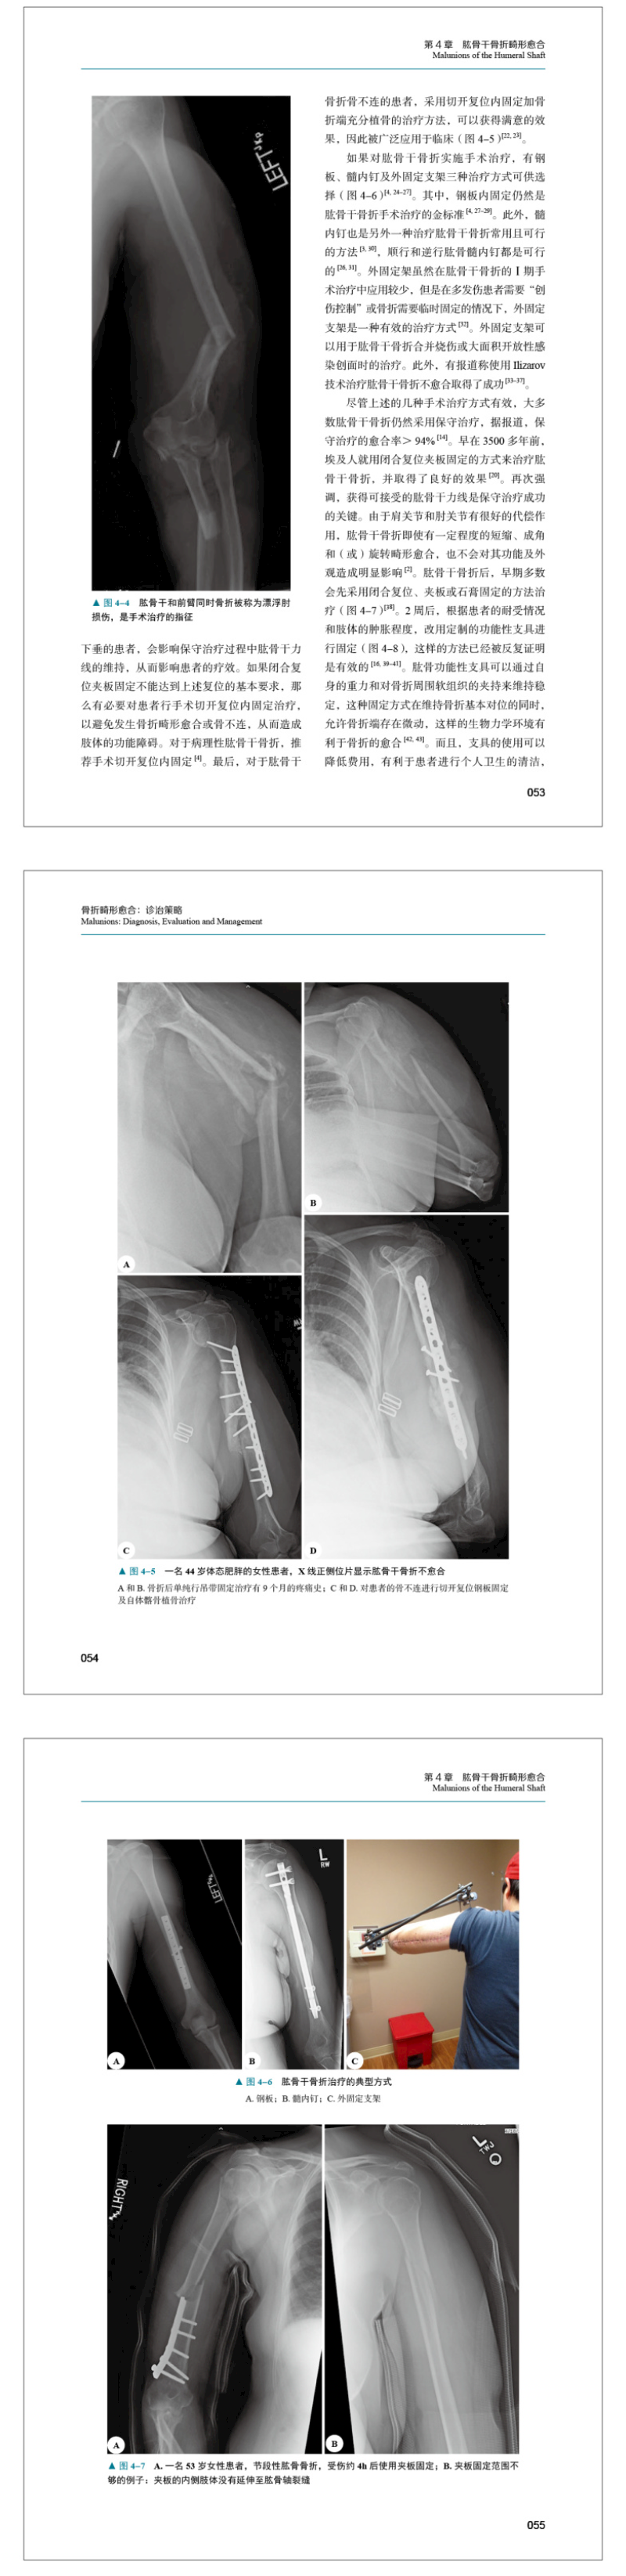

本书引进自Springer出版社,由骨折畸形愈合诊治经验丰富的专家领衔编写,是一部有关骨折畸形愈合方面的经典著作。书中所述涵盖了骨折畸形愈合的基本知识、治疗原则、常见骨折畸形愈合的术前评估、手术治疗及预防措施、经典病例讨论、著者经验及术式推荐。书中各章按解剖区域划分,不同类型的骨折畸形愈合并非采取同一种既定的解决方案,而须实行个体化治疗方案。书中所述的治疗方案都极具临床实用性,并被专家实践证实有效。在处理骨折畸形愈合时,读者可以借鉴书中提供的方案。